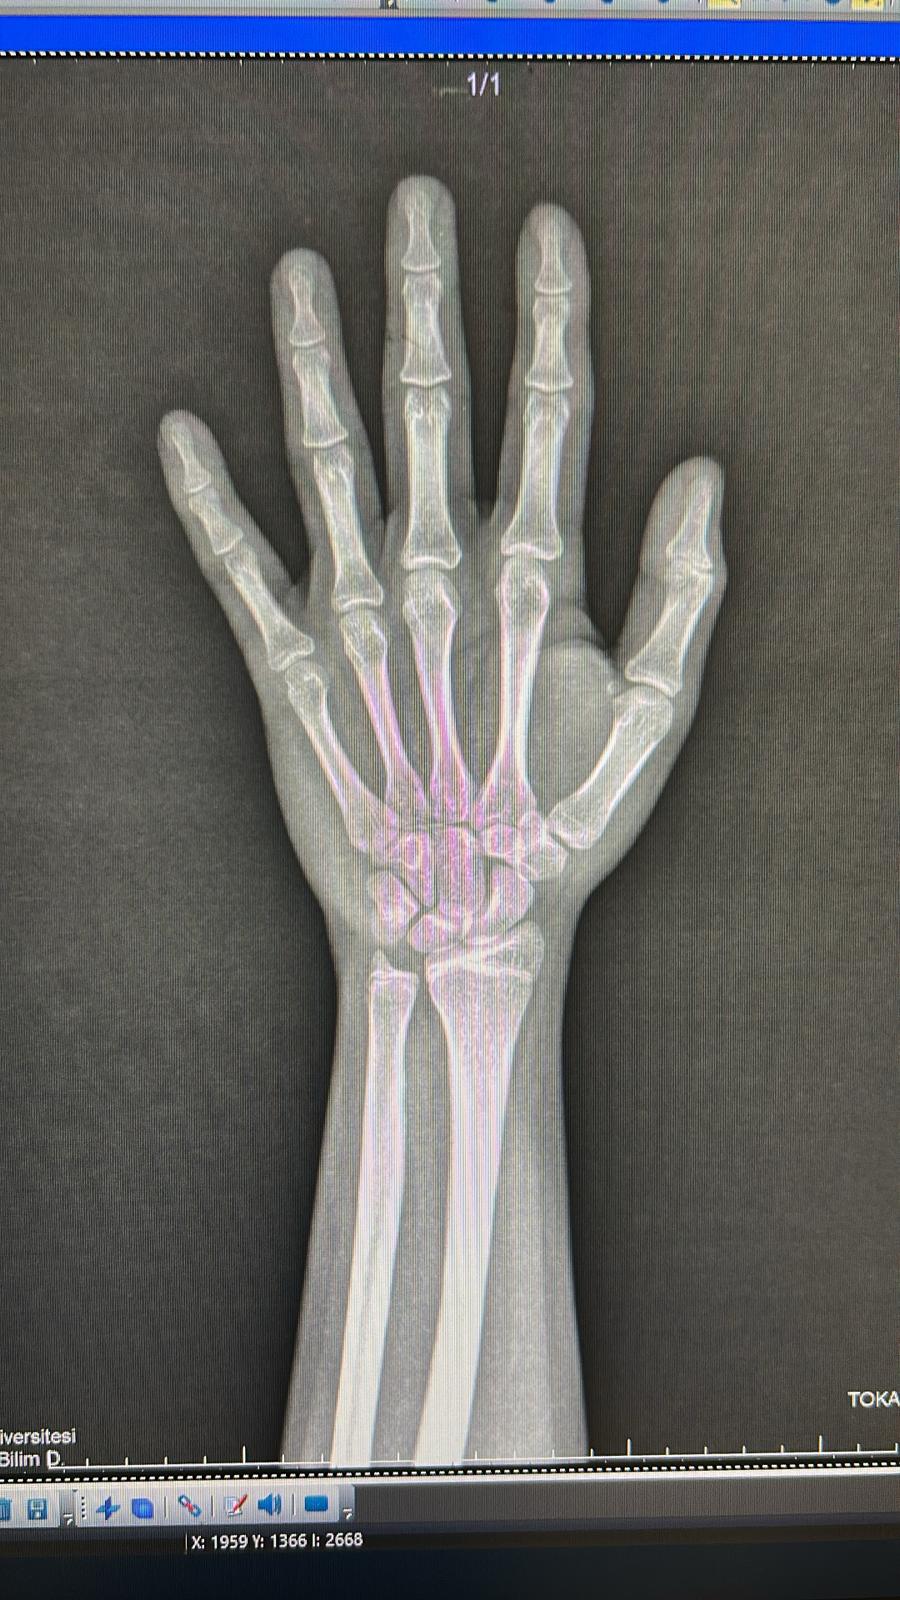

Ekimde 15e girdim ve boyum hakkında endişeliyim bilgili arkadaşlar yorumlarsa sevinirim kaç cm uzarim???

< Resime gitmek için tıklayın >

Büyüme plakların kapanmış. Daha uzamasını beklemem.

Şuradan da bakabilirsin. 18 yaşında birinin eli gibi olmuş.

EndoC Hesaplamalar | KEMİK YAŞI ATLASI